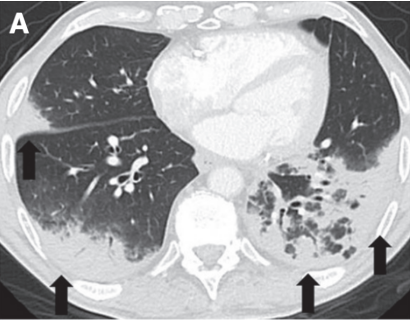

(3)非特异性间质性肺炎(NSIP):是CIP第二常见的报道类型,通常表现为肺下叶GGO和网状结构[17]

图片